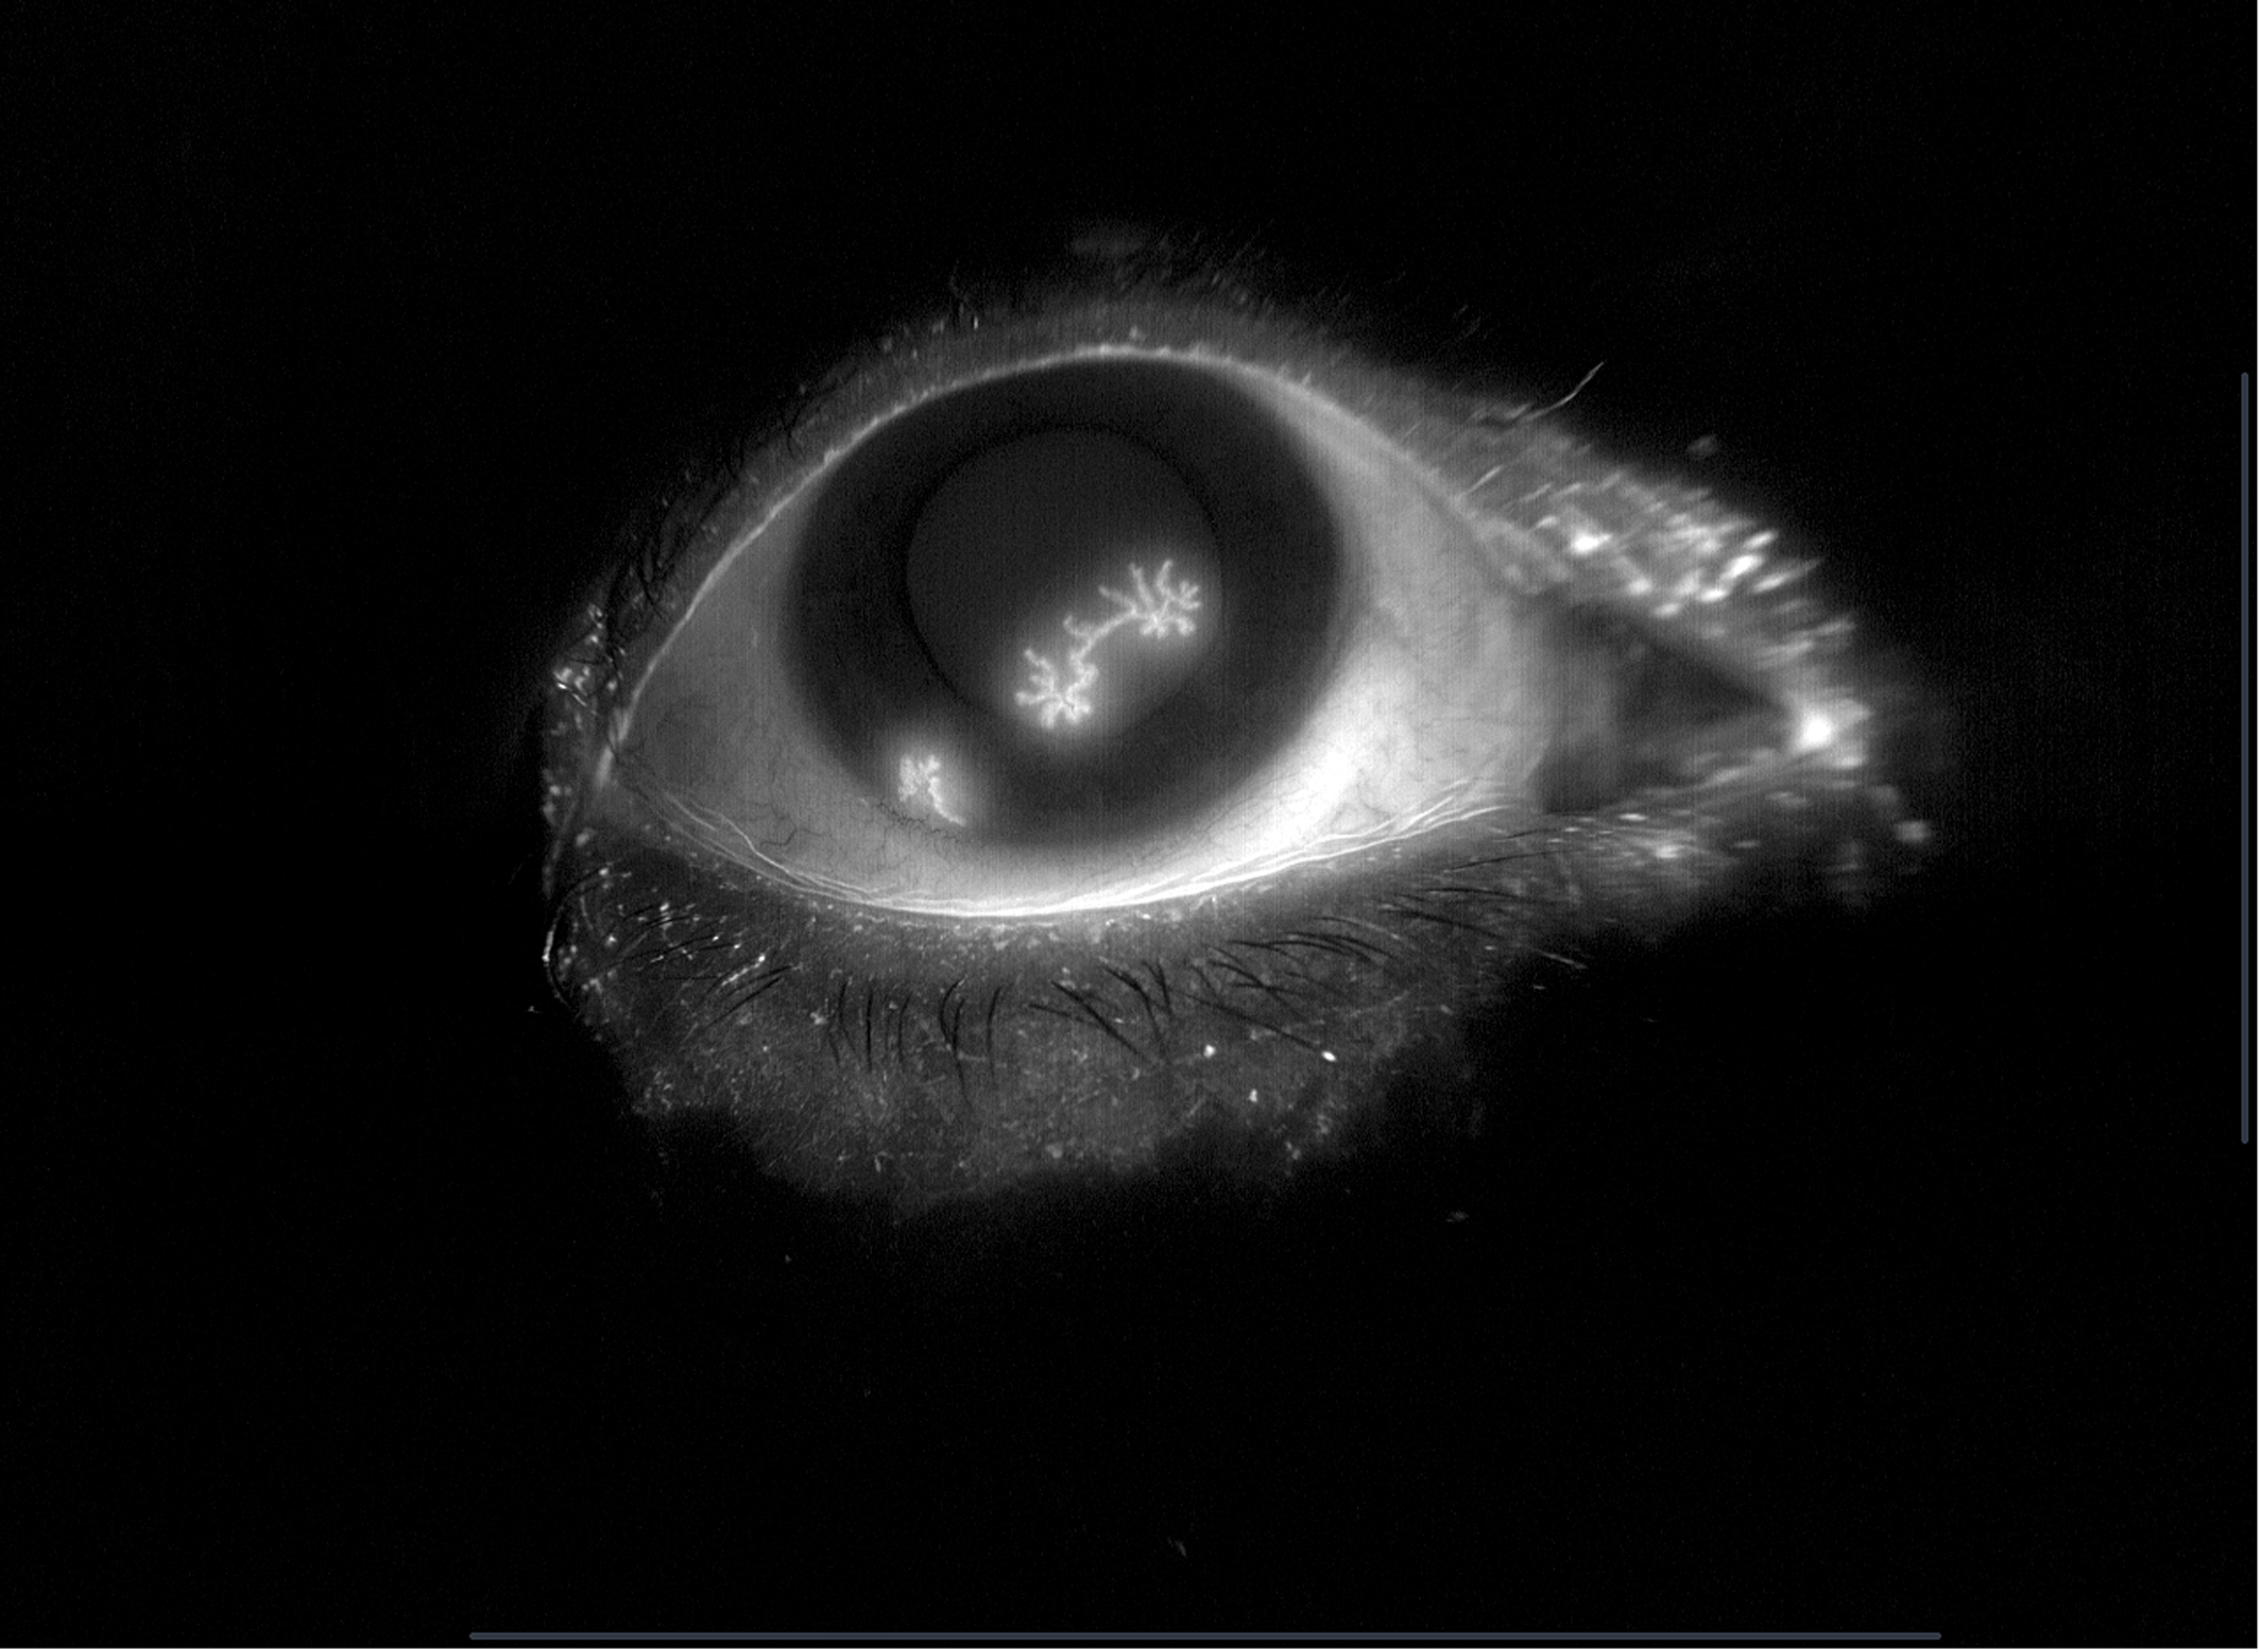

HSV Dendritic Keratitus Presented by Nareum Poolnil This photograph received First Place, External Photography in the 2025 OPS Scientific Exhibit. Filed Under Cornea OPS Photo